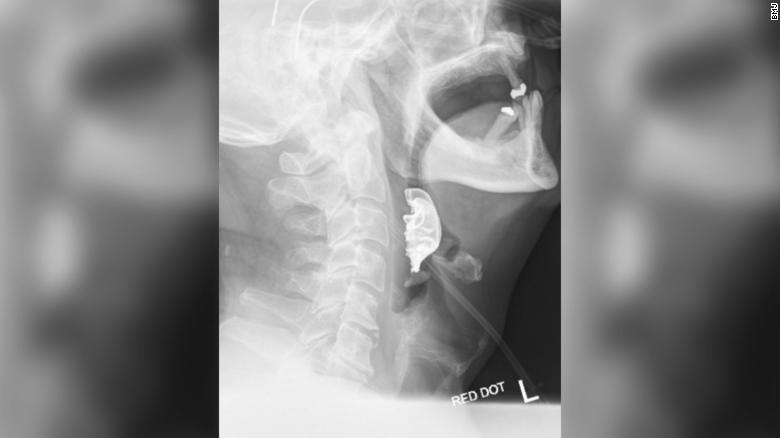

Eventually a diagnostic procedure identified a semicircular object lying across his vocal cords, which had caused internal blistering and swelling.

最終,一個(gè)診斷程序發(fā)現(xiàn)他的聲帶上橫著一個(gè)半圓形物體,導(dǎo)致了聲帶內(nèi)部起泡和腫脹。